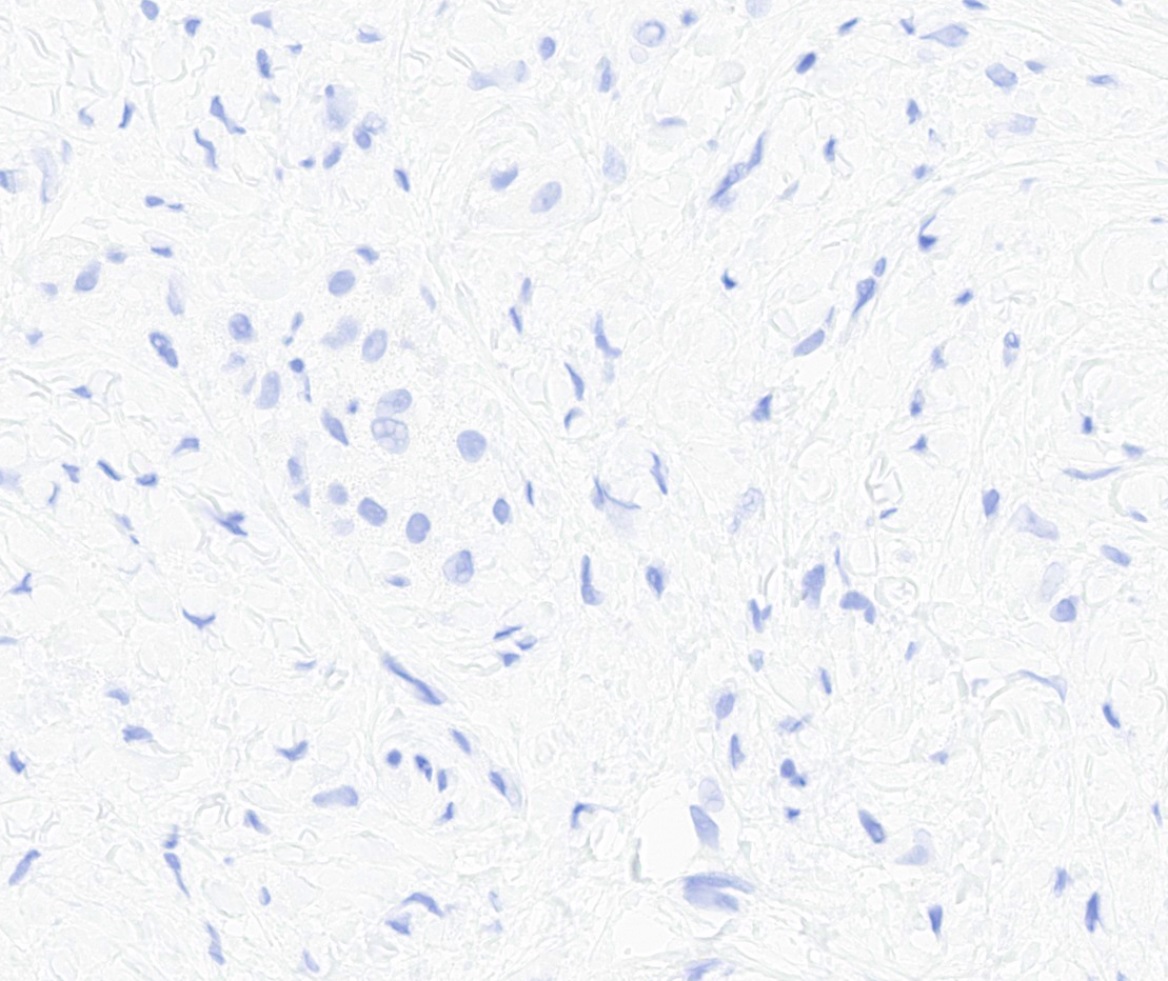

Microscopic (histologic) images

Negative stains

- Rb (negative in 89 - 92%) (Am J Surg Pathol 2016;40:361, Am J Surg Pathol 2012;36:1119)

- Actin (negative in 63%)

- Cytokeratins, S100, p63